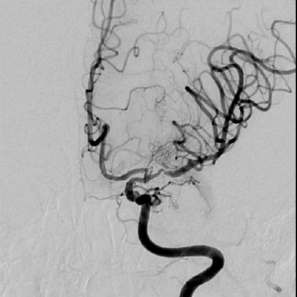

发病一周后完善了脑血管造影检查 。

正位

侧位

左侧大脑中动脉前向血流较同侧大脑前动脉缓慢。

3D:左侧颈内动脉C7段中度狭窄,左侧大脑中动脉M1段重度狭窄。